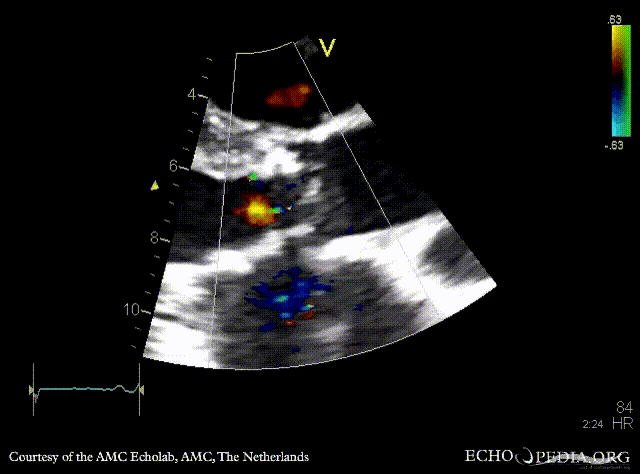

| PSAX: Color Doppler of aortic bioprosthesis